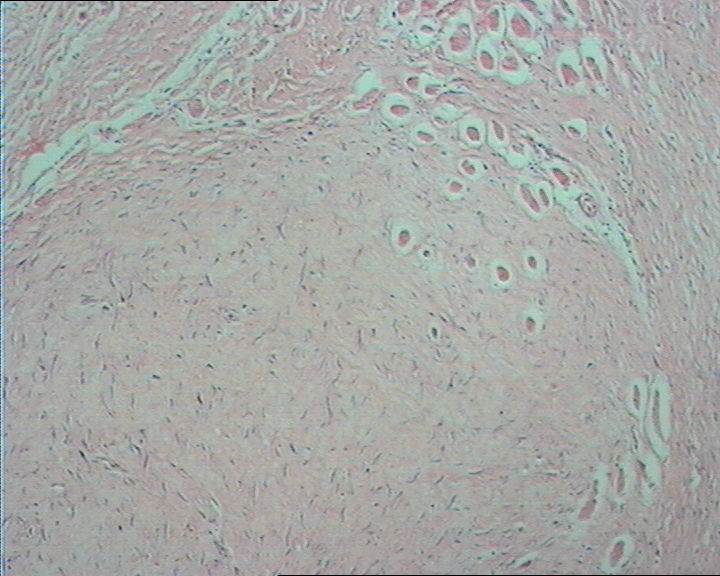

右肘部肿物

图1

右肘部肿物,无包膜,3.8cm*3.0cm*2cm,切面灰白淡黄相间。